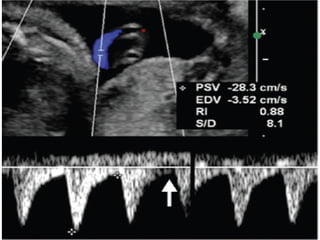

FLUJOMETRIA NORMAL A LA SEMANA 7 A 10-13

FLUJOMETRIA NORMAL ALA SEMANA 7 A 10-13